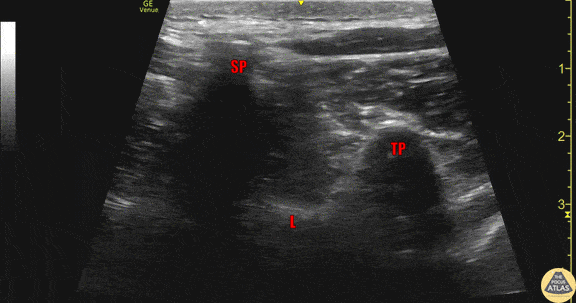

Anatomy of a thoracic vertebra as seen in transverse view, using the linear transducer. The spinous process (SP) is seen most superficially and in the midline, with the lamina (L) seen connecting the spinous process to the transverse process (TP) laterally. Sliding pleura can also be seen lateral and deep to the transverse process. Drs. Sam Paskin-Flerlage, PGY4 and Michael Heffler, PGY3 Denver Health Residency in Emergency Medicine